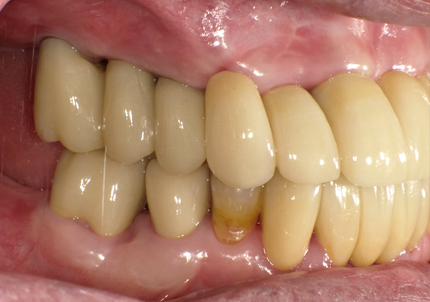

22.最終補綴物完成・装着口腔内写真(2021年1月)

23.自然な形態のインプラント歯頚部

適切な治療計画と治療技術を有することで、このような自然な形態のインプラント歯頚部を形成することができます。

24.口腔内写真

【 2025年5月 現在 】